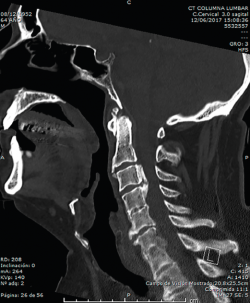

En la Figura 3 puede verse un corte sagital de la TAC cervical con sindesmofitosis también a este nivel, provocando un verdadero canal estrecho cervical en el raquis cervical alto.

Figura 3. Corte sagital de tomografía axial computarizada cervical.